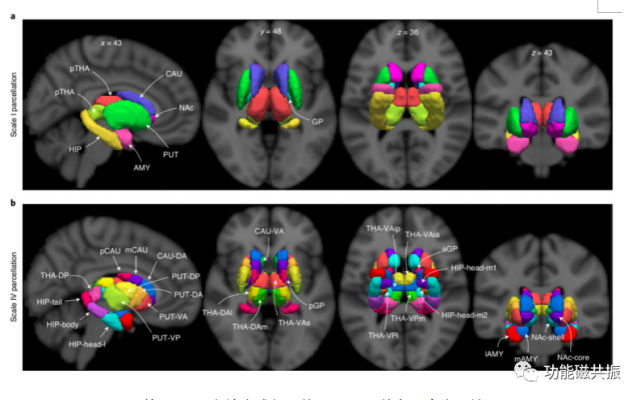

一级图谱(scaleI atlas)经过上述构建,我们得到了最大尺度的图谱:一级图谱(scale I atlas)。一级图谱重现了常见的解剖结构,一共包括16个区域,如图4a所示。

二级图谱对一级图谱递归调用上述梯度映射、边界分割和模型选择的过程可以得到更加精细的二级图谱。递归调用上述过程可以得到更加精细的图谱(二级:32区域;三级:50区域;四级(图4b):50区域)。分割流程如图5所示。

图4. 基于1080名健康成年人的3T-rfMRI的多尺度分区结果

CAU:尾状核;THA:丘脑;HIP:海马;AMY:杏仁核;PUT:壳核;NAc:伏隔核;GP:苍白球